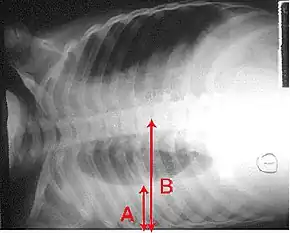

X-ray presentations of pneumonia may be classified as lobar pneumonia, bronchopneumonia, lobular pneumonia, and interstitial pneumonia.[66] Bacterial, community-acquired pneumonia classically show lung consolidation of one lung segmental lobe, which is known as lobar pneumonia.[34] However, findings may vary, and other patterns are common in other types of pneumonia.[34] Aspiration pneumonia may present with bilateral opacities primarily in the bases of the lungs and on the right side.[34] Radiographs of viral pneumonia may appear normal, appear hyper-inflated, have bilateral patchy areas, or present similar to bacterial pneumonia with lobar consolidation.[34] Radiologic findings may not be present in the early stages of the disease, especially in the presence of dehydration, or may be difficult to interpret in the obese or those with a history of lung disease.[21] Complications such as pleural effusion may also be found on chest radiographs. Laterolateral chest radiograph can increase the diagnostic accuracy of lung consolidation and pleural effusion.[33]